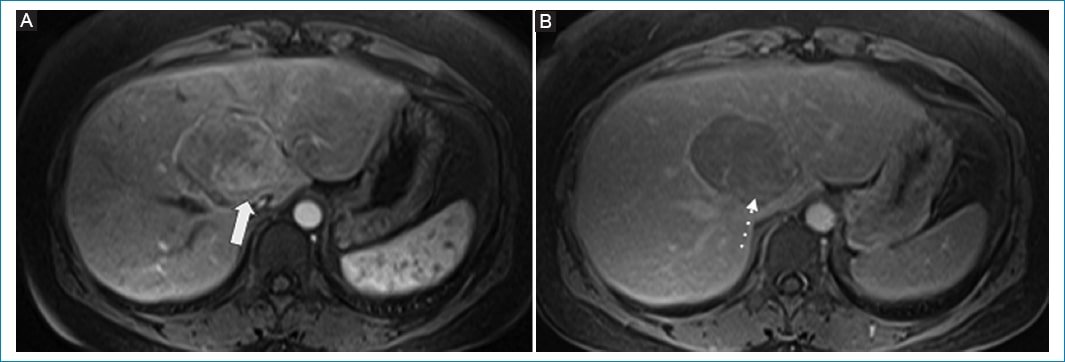

Presentamos el caso de una mujer de 34 años, sin antecedentes médicos relevantes, que fue remitida a nuestro centro por el hallazgo incidental de un tumor hepático en una ecografía debido a dolor abdominal. Se realizó una resonancia magnética (RM) hepática con contraste endovenoso en nuestro centro, que mostró una masa heterogénea en el segmento VIII-IV de 64 x 54 mm, ligeramente hipointensa en T1, ligeramente hiperintensa en T2, con restricción en difusión y realce heterogéneo con el contraste endovenoso en la fase arterial y lavado en la fase tardía (Fig. 1–Fig. 3). No se observó infiltración de estructuras vasculares. Se interpretó como una lesión maligna, pudiendo corresponder a un carcinoma hepatocelular (HCC) o a un adenoma maligno.

Figura 3. RM hepática. Axial T1 con saturación grasa y contraste intravenoso en fase arterial (A) y tardía (B) muestra la lesión hepática con un realce heterogéneo e intenso en fase arterial (flecha) y lavado en fase tardía (flecha punteada).